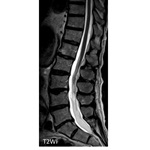

#AJNRcc >> November 11, 2024 >> What is the diagnosis for this 54-year-old woman admitted for paresthesia of the lower limbs with laboratory tests revealing an HIV infection? Submit your answer at https://t.co/6aANs07WZ8.